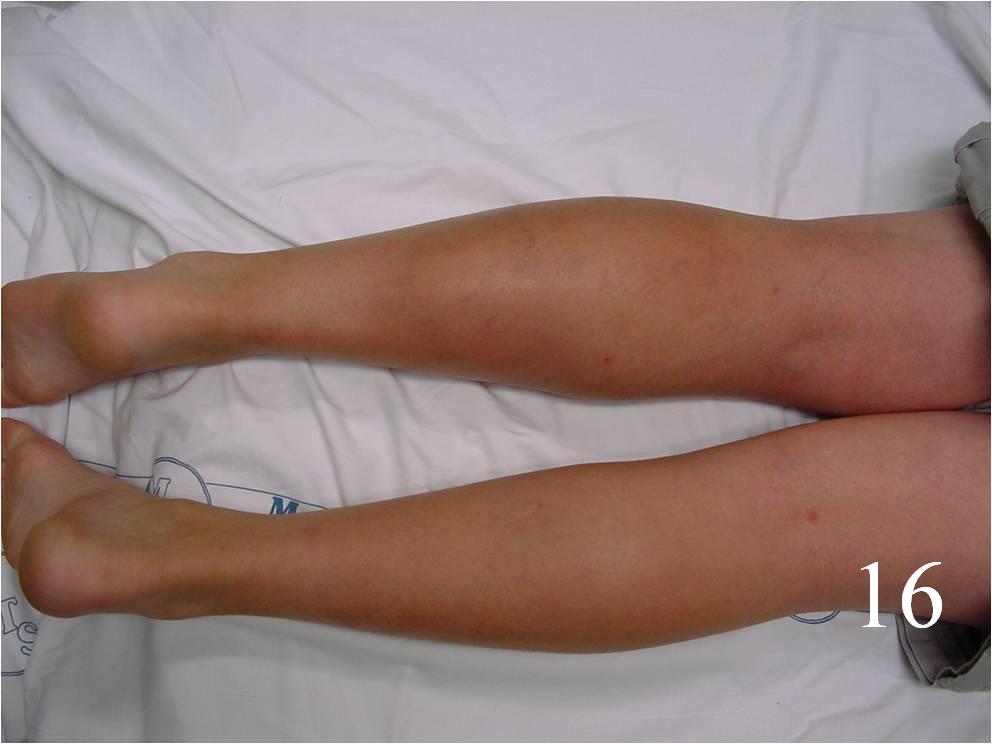

- Surgery: wide resection, chemotherapy, and possible radiation (Fig. 16-19)

Fig. 16-18: Intraoperative photograph shows a big rhabdomyosarcoma in the left calf. Photograph of a radical resection (Fig. 17) of the rhabdomyosarcoma to the calf. After the resection of the tumor (Fig. 18), multiple rotational flaps are performed to fill the dead space,